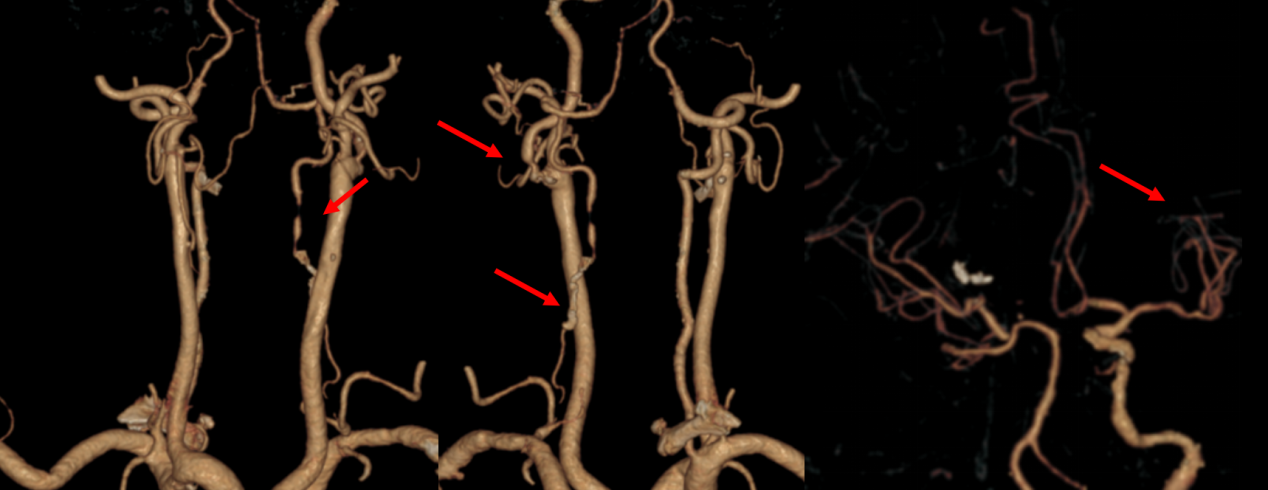

增强血管检查:红色箭头部分为右侧颈内动脉陈旧闭塞,左侧颈动脉狭窄,左侧椎动脉狭窄